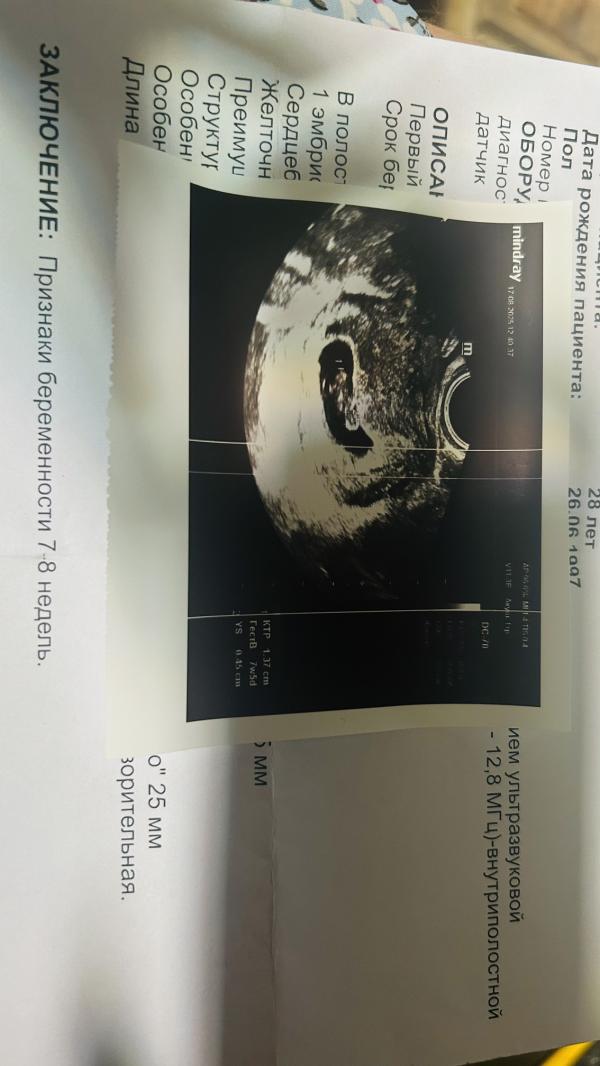

Девочки, все отлично) растет, сердечко бьется ❤️